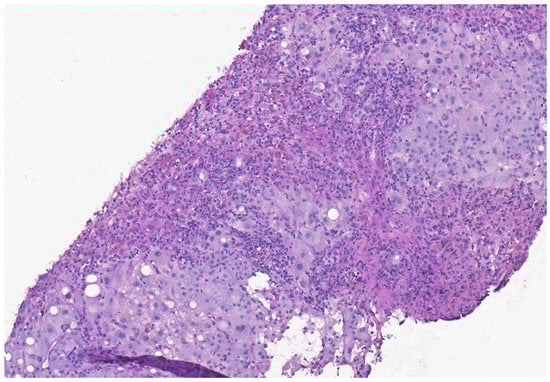

2. Case Presentation